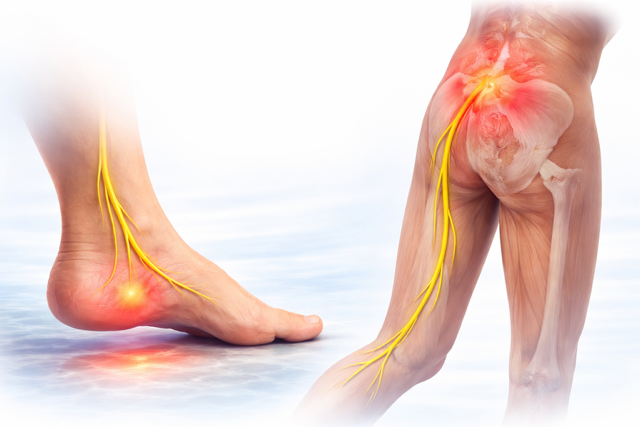

¿Es posible que el origen del dolor lumbar esté en mis pies?

Sí , por supuesto, de hecho, es una de las causa más comunes, el factor biomecánico. Y ocurre mucho más de lo que imaginas.

El cuerpo no funciona por piezas aisladas, sino como una cadena biomecánica. Cuando un eslabón falla —como el pie—, el resto del sistema compensa.

El problema es que esas compensaciones, con el tiempo, generan dolor lejos del origen.

¿Puede ser por que tengo un pie plano ?

El pie plano provoca un colapso del arco plantar.

Ese pequeño gesto tiene un efecto en cadena:

– El tobillo cae hacia dentro

– La tibia rota internamente

– El fémur sigue esa rotación

– La pelvis se descompensa

– La columna lumbar intenta adaptarse

Lo que empezó en el pie, termina en tu zona lumbar.

¿Entonces tiene sentido que me duela la espalda y el talón ?

Si , claro. Tiene todo el sentido ya que hay una conexión directa entre ambos, tanto a nivel biomecánico , como de conexión nerviosa.